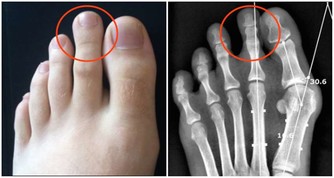

馬德龍綜合徵是一種因長期飲酒,導致脂肪代謝紊亂,在皮下等部位對稱、過度堆積而形成一種病症。脂肪常會堆積在頭部、頸部、肩部以及腰部等部位,上下肢呈現近端肥胖、遠端細小,類似動漫“大力水手”的手臂外形。

患者常因堆積脂肪組織壓迫氣管、食管,出現呼吸困難和吞嚥受阻而就診。

發病特點,多為男性,有長年飲酒史,有的飲酒史長達20到30年之久,飲酒量大,每天飲酒在1.5斤至2斤。